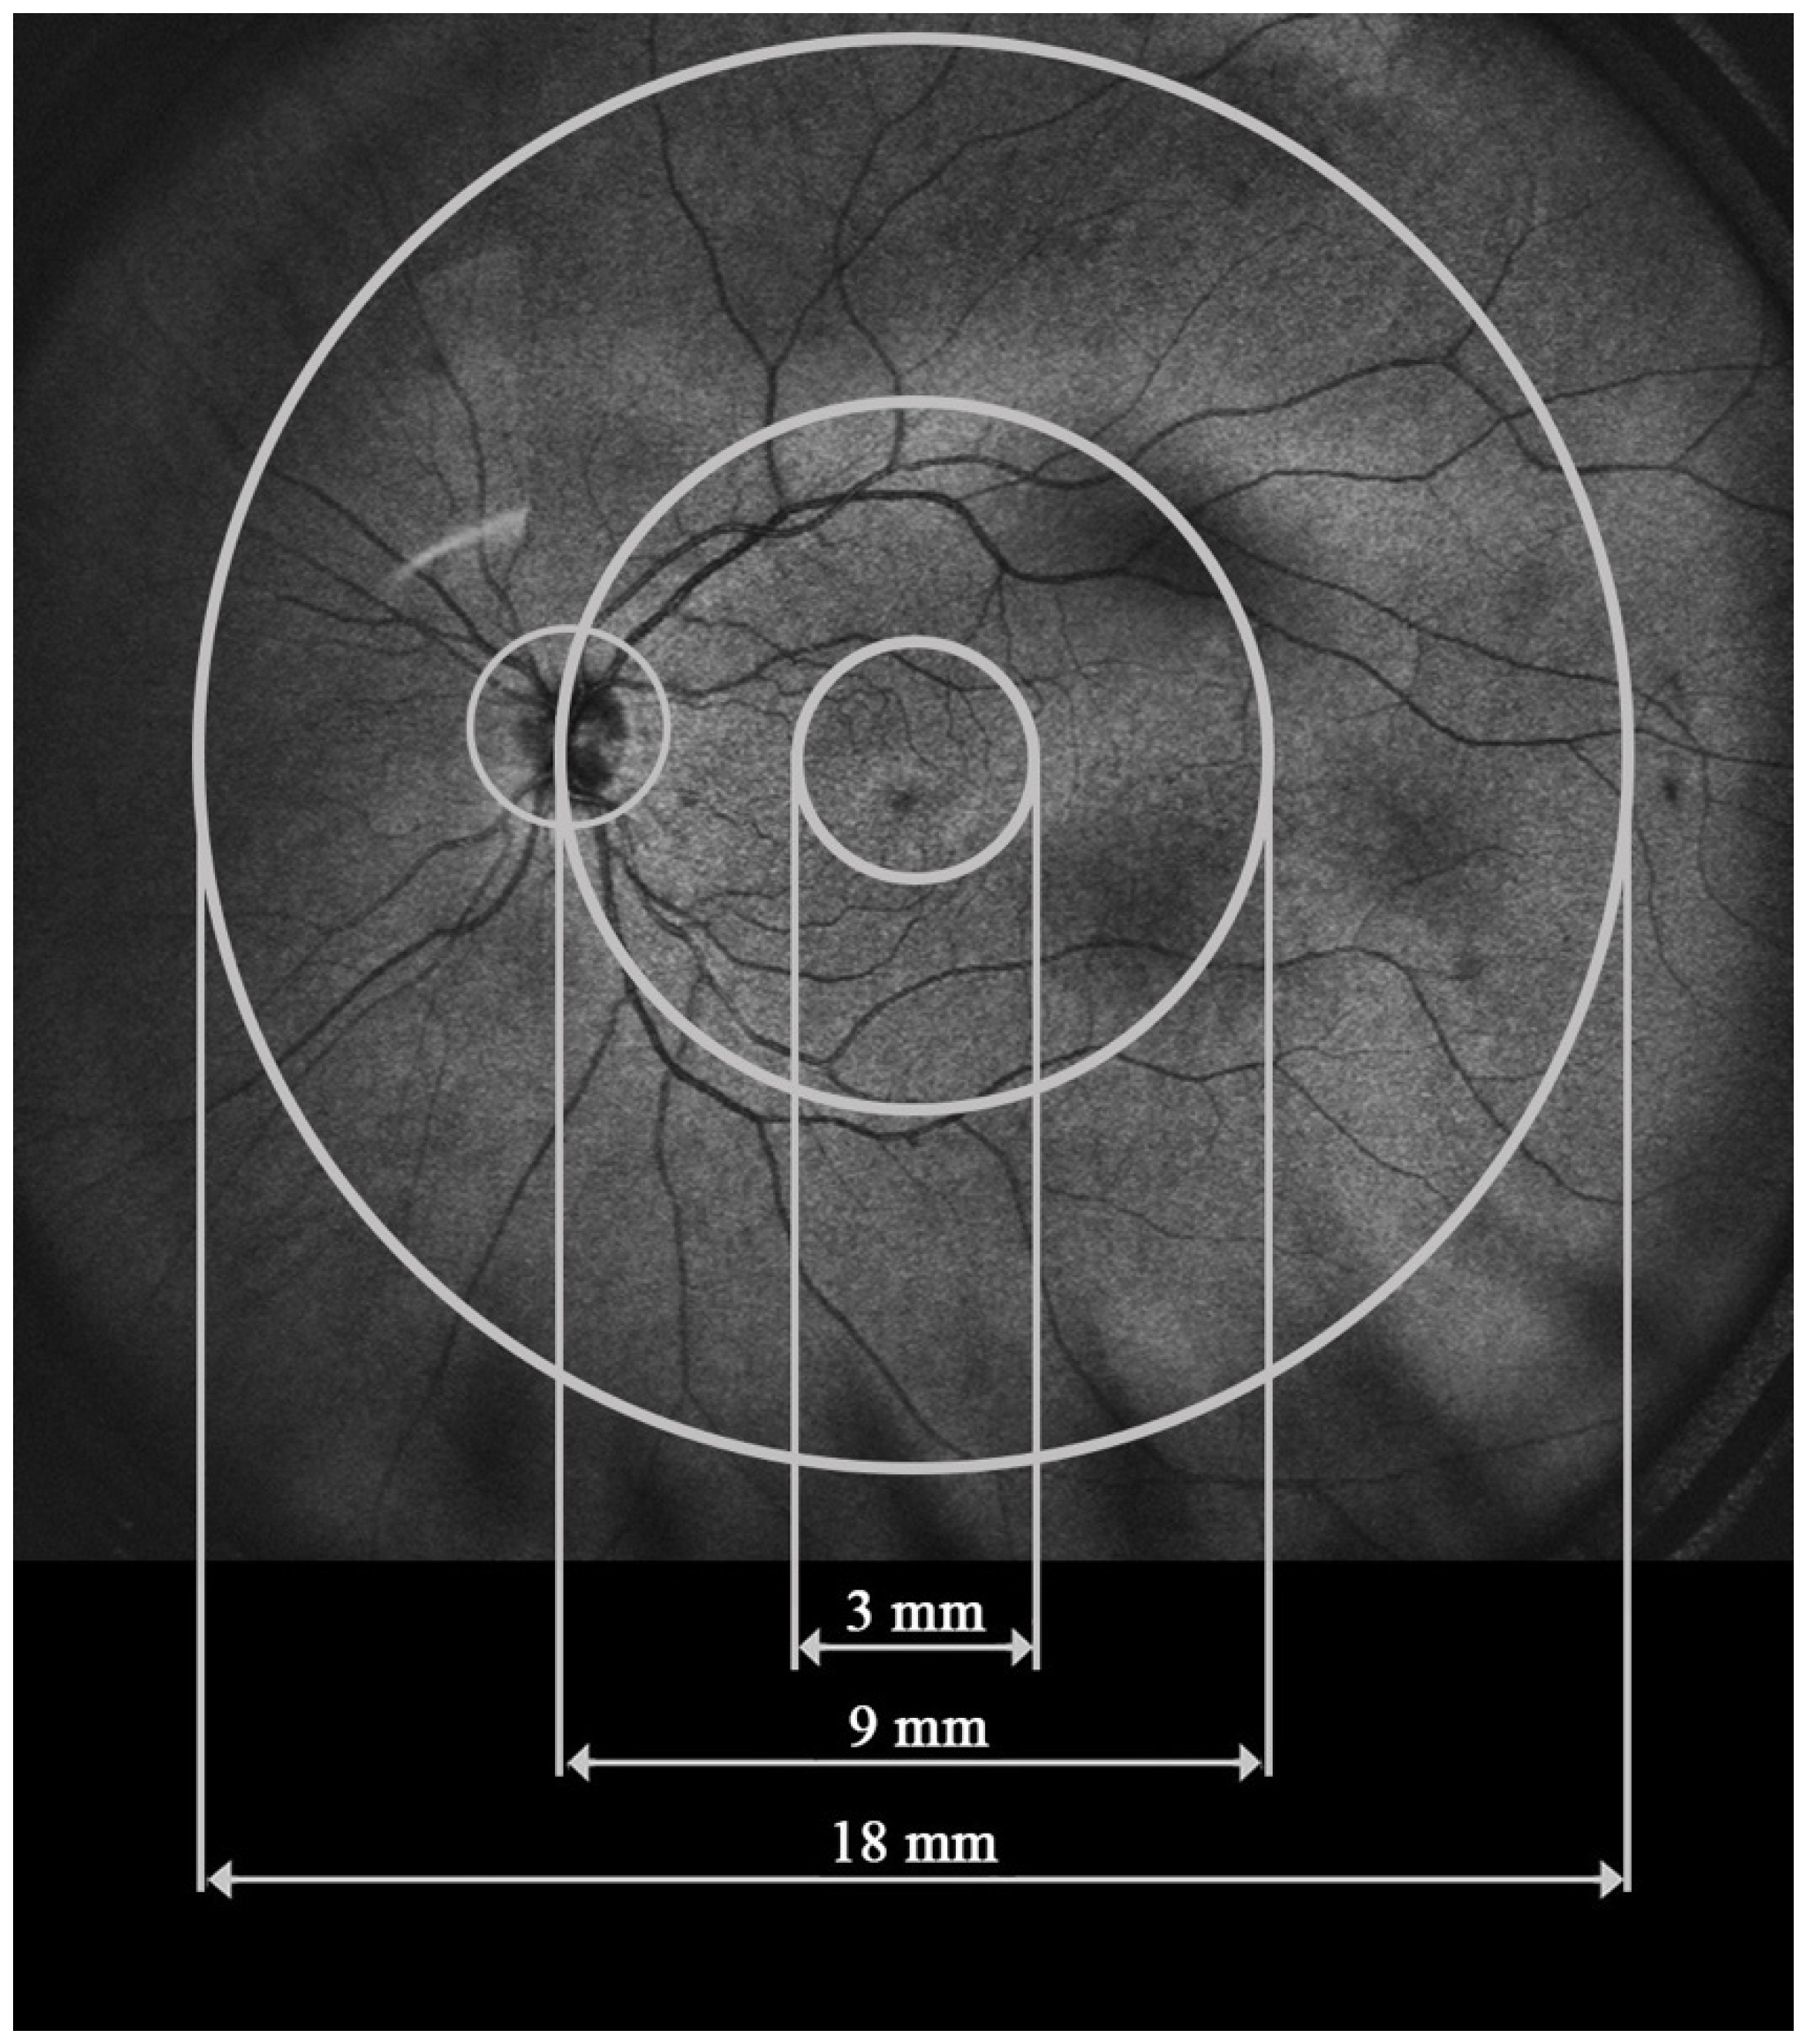

UWF-OCT testing was performed in all study participants after pupil dilation using a new swept-source device, the Xephilio OCT-S1 (Canon Medical Systems Europe B.V., 2023, Amstelveen, The Netherlands). This device provides scanning of the retina and choroid over a large area of 20 × 23 mm with a single acquisition and the speed of 10,000 A scans per second. The protocol for RT and CT measurements includes 25 fields enclosed in a large circular area of 18 mm in diameter. For the purpose of our study, the measured sectors were merged into three zones extending from the center to the periphery: the central circle, 3 mm in diameter (central), the ring between the central 9 mm circle and the central 3 mm circle (perifoveal), and the second, more peripheral ring between the central 18 mm and 9 mm circles (peripheral) (Figure 1). RT and CT values presented for each zone in our study stand for the arithmetic mean calculated from the values provided for smaller sectors by the Xephilio OCT-S1 device.

Figure 1.

Retinal and choroidal zones analyzed in the study with UWF-OCT.